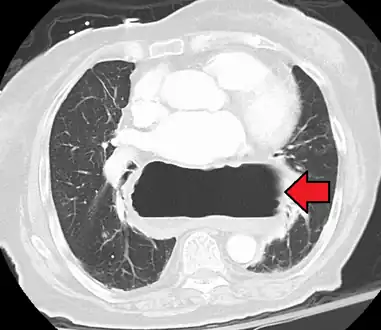

Diagnosis

The diagnosis of a hiatal hernia is typically made through an upper GI series, endoscopy, high resolution manometry, esophageal pH monitoring, and computed tomography (CT). Barium swallow as in upper GI series allows the size, location, stricture, stenosis of oesophagus to be seen. It can also evaluate the oesophageal movements. Endoscopy can analyse the esophageal internal surface for erosions, ulcers, and tumours.

Meanwhile, manometry can determine the integrity of esophageal movements, and the presence of esophageal achalasia. pH testings allows the quantitative analysis of acid reflux episodes. CT scan is useful in diagnosing complications of hiatal hernia such as gastric volvulus, perforation, pneumoperitoneum, and pneumomediastinum.[8]